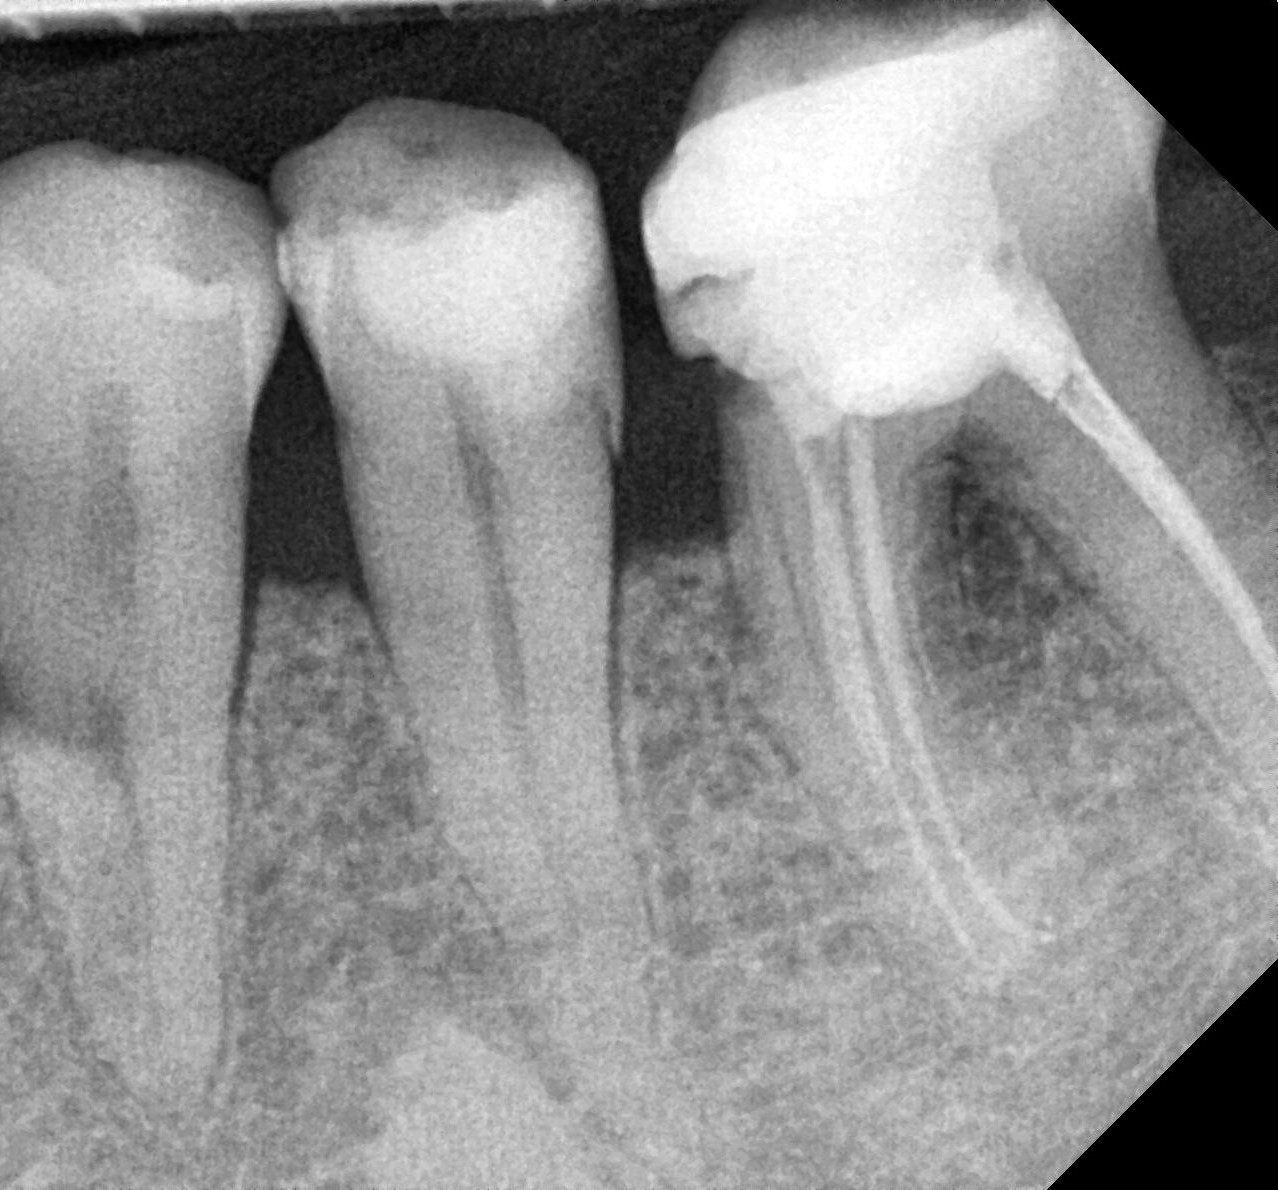

Zgłosił się do mnie pacjent, którego skierowano do specjalisty periodontologa w celu konsultacji i leczenia ubytków kostnych w okolicy zębów 34-36. Pacjent jest ogólnie zdrowy. W trakcie wywiadu ogólnostomatologicznego zgłaszał dyskomfort oraz krwawienie dziąseł podczas szczotkowania zębów, utrzymujące się od wielu miesięcy. Na zdjęciu RTG celowanym dostarczonym przez pacjenta stwierdziłam ubytki nadkostne w okolicy 34-36. Jakie działania powinnam podjąć?

W opisanym przypadku stwierdzono: złogi naddziąsłowe i poddziąsłowe, uogólniony obrzęk i zaczerwienienie dziąseł, krwawienie – BOP >70%. Głębokość sondowania oceniono w 6 punktach przy wszystkich zębach. Otrzymane wartości oscylowały w granicach 5-8 mm, w okolicy zęba 35 na powierzchni dalszej wartość PD wynosiła 9 mm.

W przypadku, gdy pacjent osiągnął prawidłową higienę jamy ustnej (FMPS<20%), ale utrzymuje się stan zapalny (BOP+), a PD ≥5,5 mm, można rozważyć leczenie chirurgiczne. Obecność ubytku nadkostnego skłania do wyboru minimalnie inwazyjnego zabiegu oczyszczenia po podniesieniu płata (open flap debridement – OFD). Zabieg taki pozwala na eliminację zapalenia i spłycenie kieszonek patologicznych, ale może też generować recesję dziąsła. Dlatego wykonanie OFD w odcinku przednim jest przeciwwskazane. Widoczne na RTG nadkostne ubytki w okolicy 34-36 nie dają możliwości odtworzenia tkanek przyzębia, a więc są przeciwwskazaniem do periodontologicznych zabiegów regeneracyjnych.

Ryc. 1. Nadkostne ubytki w okolicy 34-36.